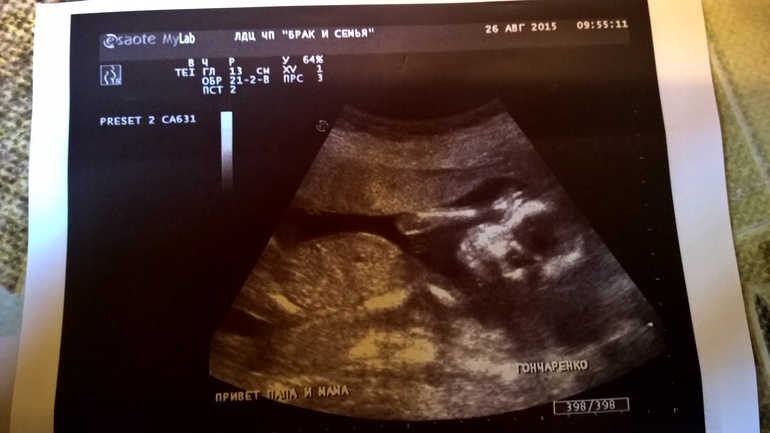

Ура! Узнали кто там живет😊

Были сегодня на узи, все хорошо😊

Обрадовали нас! У нас будет... ДЕВОЧКА!💝 солнышко наше☀ я рада!! Муж тоже😍 перекрашиваю кружок в розовый))